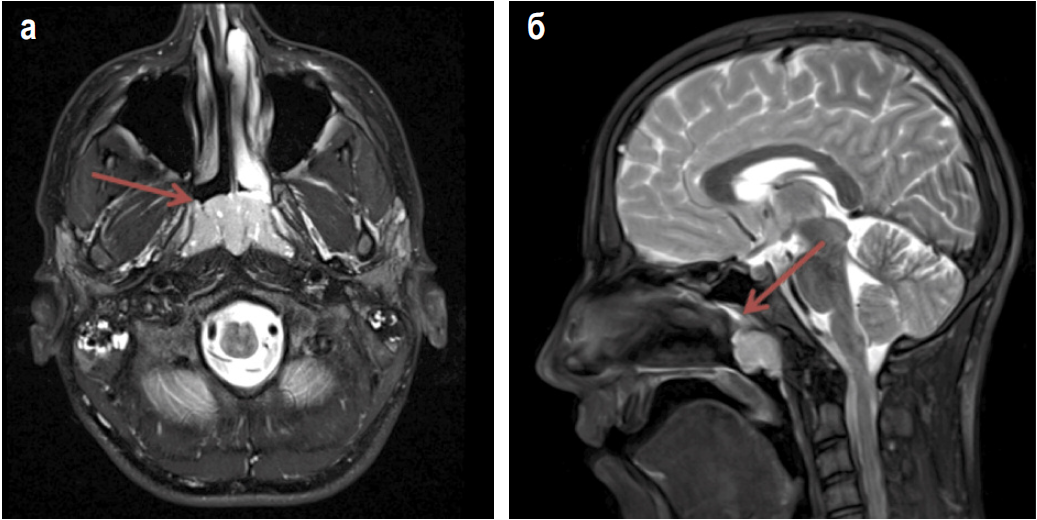

Результаты компьютерной томографии (КТ) с контрастным усилением, выполненной до начала лечения, показали, что в области свода носоглотки и по задней стенке определяются патологические ткани, перекрывающие ее просвет, переходящие на небные миндалины, неоднородно и активно накапливающие контрастный препарат размером 37×42×78 мм. Размер шейно-подчелюстных лимфатических узлов – 36×40×54 мм. Признаков деструкции костей, вошедших в исследование, не выявлено. Результаты КТ представлены на рис. 1.

Рис. 1: а – стрелкой показаны патологические ткани в носоглотке, перекрывающие ее просвет, переходящие на небные миндалины, неоднородно накапливающие контрастный препарат; б – стрелкой показано практически полное сужение просвета носоглотки.

Fig. 1: a – the arrow shows pathological tissues in the nasopharynx, blocking the lumen, involving the palatine tonsils, heterogeneous accumulating contrast drug; b – the arrow shows almost complete narrowing of the nasopharynx lumen.